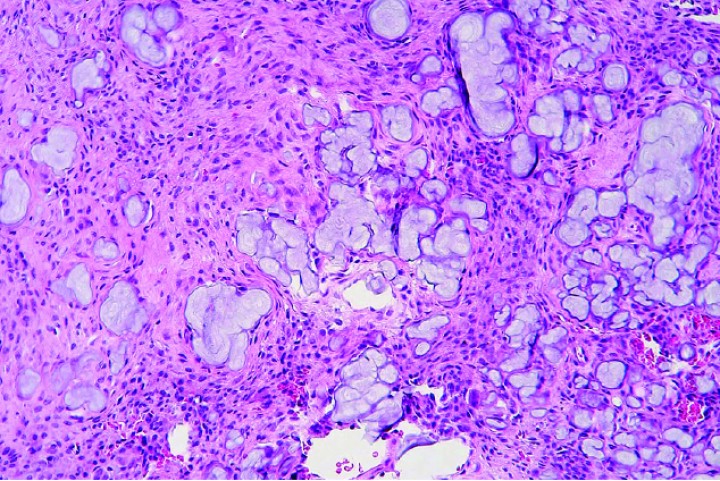

Histológicamente, estos condrosarcomas se caracterizaban por una proliferación de células poliédricas a fibrohistiocíticas o, más raramente, fusiformes dispuestas en nidos, haces o de forma sólida, con depósitos dispersos intercelulares de matriz basófila o anfofílica densa y, en algunos casos, matriz fibrilar eosinofílica que mostraba osificación endocondral o mineralización variable (Figs. 5, 6 y 7); ocasionalmente, se apreciaban zonas con estroma fibroso (Fig. 8).

<div class=\"Basic-Text-Frame\">

<p>Cobaya 2. Imagen microscópica de la biopsia de masa craneal. Se observa producción de abundante matriz cartilaginosa (asteriscos) por nidos de condrocitos neoplásicos dispersos entre dicha matriz. (Hematoxilina y eosina, x40).</p>

Figura 5

Cobaya 2. Imagen microscópica de la biopsia de masa craneal. Se observa producción de abundante matriz cartilaginosa (asteriscos) por nidos de condrocitos neoplásicos dispersos entre dicha matriz. (Hematoxilina y eosina, x40).